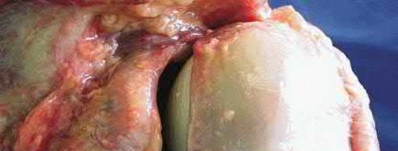

3. # Which of the following is not an appropriate implant for treatment of the fracture seen in Figure A?

The image shows a reverse obliquity intertrochanteric hip fracture.

According to the referenced article by Haidukewych et al, unstable peritrochanteric hip fractures have a worse outcome (failed in 9/16 cases) if treated with a sliding hip screw. Two additional factors that were found to have a strong correlation with postoperative failure (nonunion, loss of reduction) were poor reduction and poor implant placement. In this study, fixed angle devices were superior. Intramedullary fixation has the added advantage of a shorter lever arm and less potential for fracture collapse and limb shortening.

The IMN also acts as a medial buttress.

According to Sanders et al, the dynamic condylar screw (DCS) can also be used in subtrochanteric models, but should not be used if extensive comminution is seen, as they reported a high failure rate with DCS in these fractures if highly comminuted. They report a 77% overall union rate with this device.